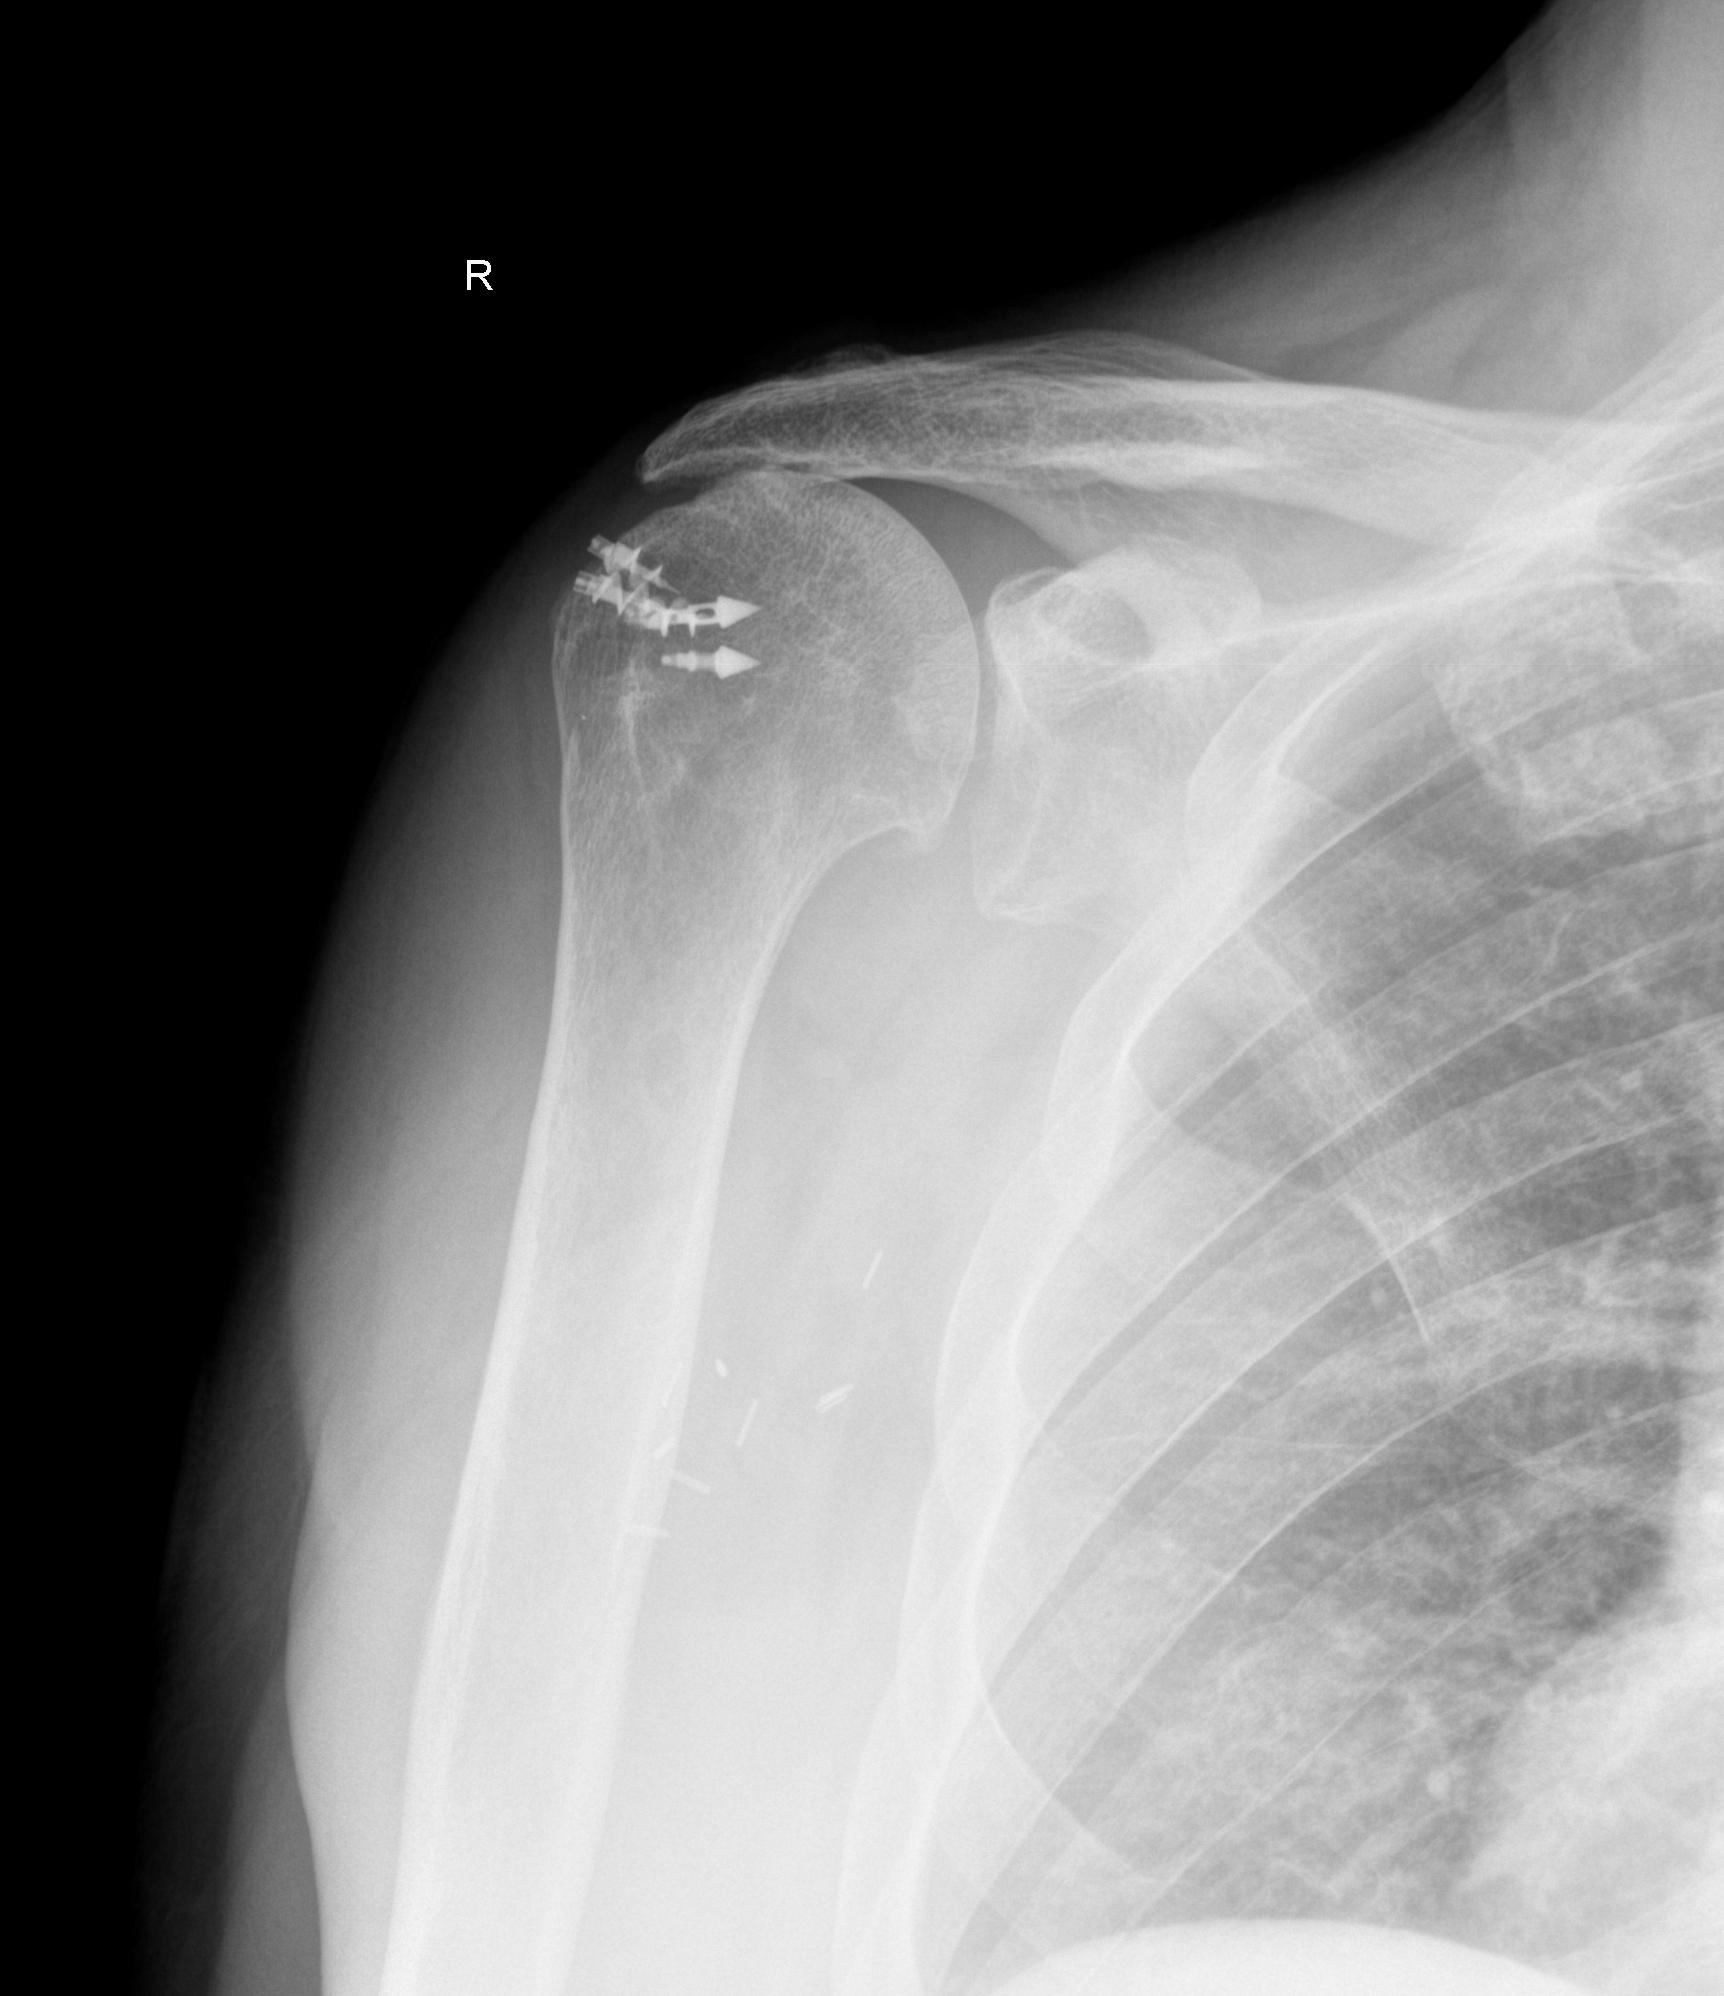

Xray imaging after arthroscopic rotator cuff repair using a suture Shoulder X Ray Rotator Cuff Tendinitis — inflammation of the rotator cuff tendons. the rotator cuff is a group of muscles and tendons that surround the shoulder joint, keeping the head of the. rotator cuff tears are one of the most common causes of shoulder pain mostly in older patients. the rotator cuff is a common cause of pain in the shoulder.. Shoulder X Ray Rotator Cuff.